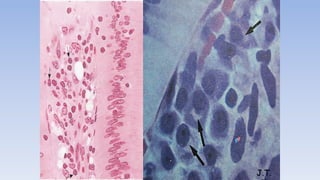

• EOSINOFILOS; no son abundantes en el t.c.

humano, pero si en las glándulas mamarias

durante la lactancia, en las vías respiratorias

y digestivas.

• Su núcleo es reniforme o bilobulado y el

citoplasma contiene gránulos esféricos muy

refringentes.

• Se acumulan en la sangre y en los tejidos en

estado alérgicos e inflamatorios subagudos

provocados por enfermedades parasitarias.